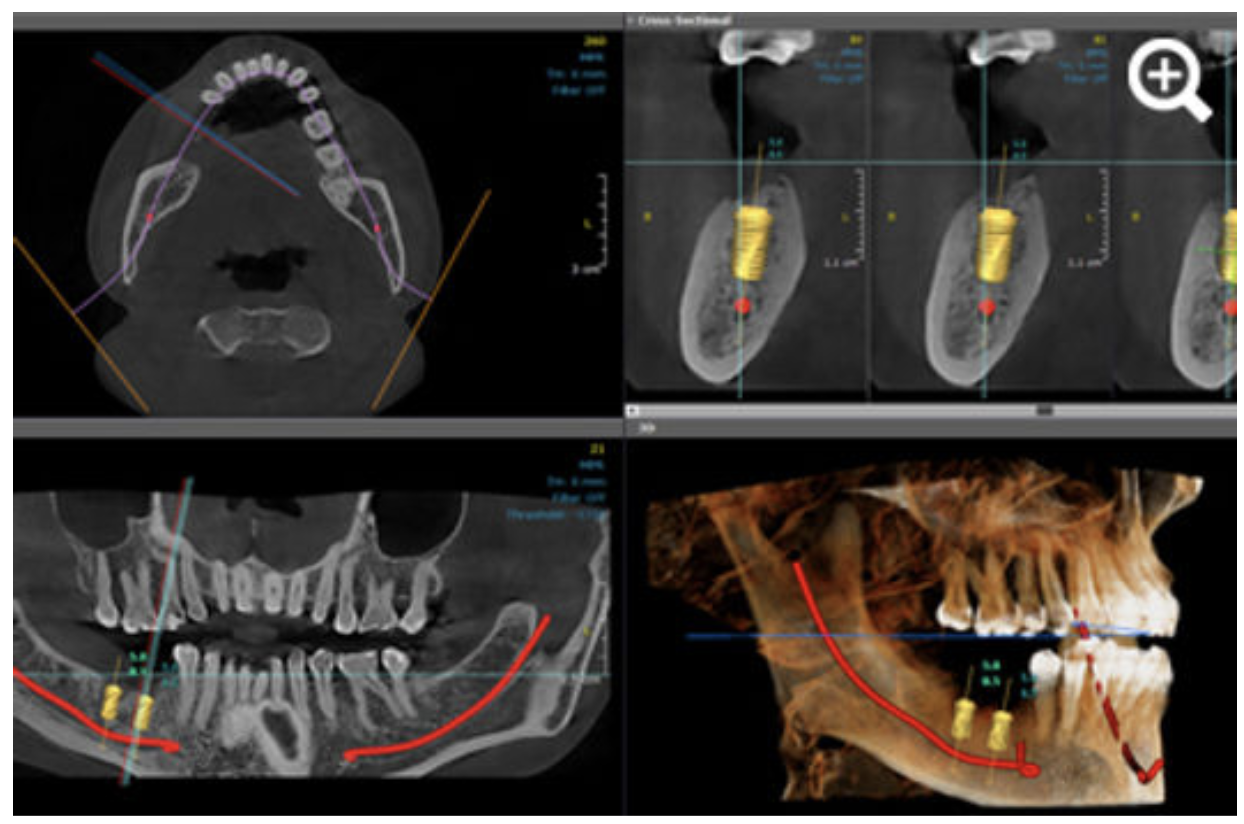

If you’re planning an implant, CBCT becomes critical.

Dentists use it to:

Without CBCT: Implant placement relies on estimation

With CBCT: It becomes data-driven and predictable

In CBCT workflows, AI plays a different role.

Instead of marking only, it supports report creation and structuring.

This enables:

Faster report generation

Reduced manual effort

Lower chances of missing key observations

However: The final report is always reviewed, validated, and concluded by a radiologist

Nidaan’s workflow is intentionally designed to maintain clinical accountability.

CBCT is essential for implant planning because it provides a complete 3D view of bone structure and nerve location.

With CBCT, dentists can:

This reduces risks such as nerve damage or implant failure and leads to more predictable long-term outcomes.